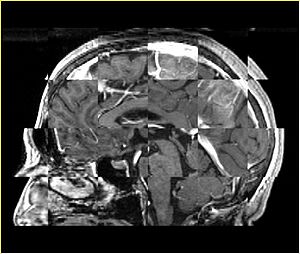

• Checkerboard appearance of unregistered images for the representative data of interest

• Case10